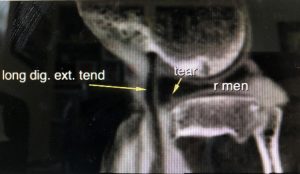

This is a CT scan with contrast media of Hank, Dr. Greene’s dog. The image is of Hank’s right knee joint which he hurt running through the woods. Our CT scan with contrast media can show many things that an MRI can show but at a fraction of the cost. Hank has a lateral meniscus tear that will require surgery to repair it. Everybody wish Hank good luck and a speedy recovery!